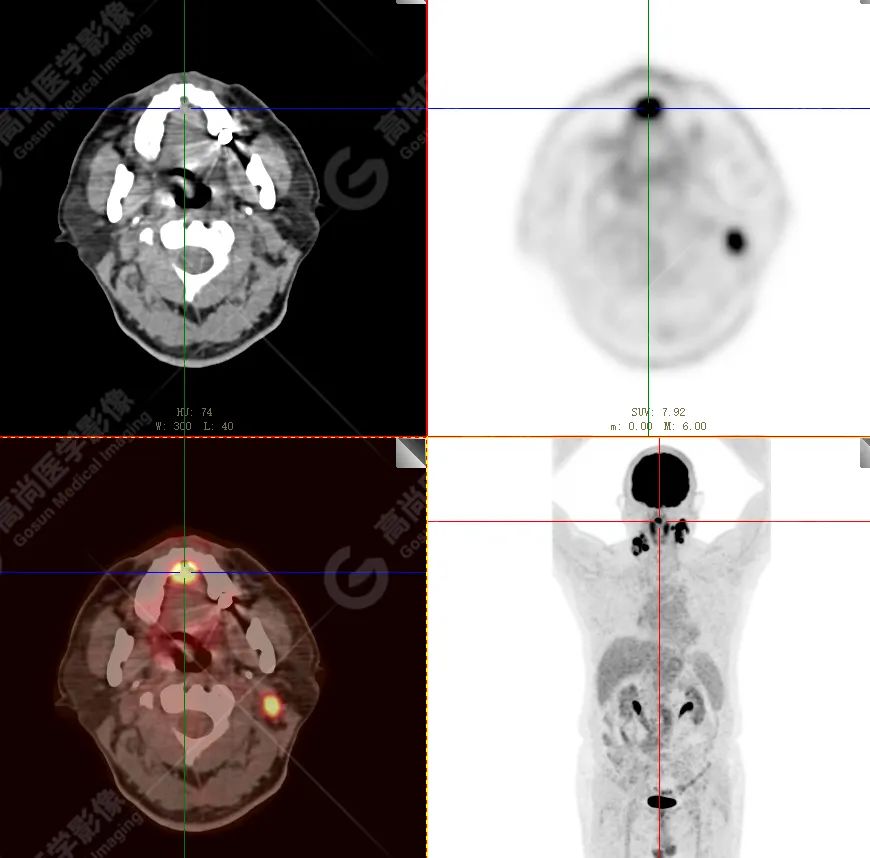

PET/CT 示:

上腭前部见一结节状放射性摄取增高影,大小约 1.6 cm×1.4 cm×1.0 cm,SUV 最大值为 10.5,CT 于上述部位见软组织密度影,边界不清,CT 值约 73 Hu(假牙金属伪影较多致 CT 值偏高)。右侧颈部(Ⅱ、Ⅲ区)及左侧颈部(Ⅰb、Ⅱ、Ⅲ区)见多发结节状及块状放射性摄取增高影,最大约 2.7 cm×2.6 cm×3.1 cm,部分放射性摄取增高,SUV 最大值为 17.7,部分病变内见放射性减低区,CT 于上述部位见增大淋巴结影。

PET/CT 结论:

1. 上腭前部结节状高代谢病灶,多考虑为恶性肿瘤(结合病史,较倾向于黑色素瘤),请结合病理学检查。

2. 右侧颈部(Ⅱ、Ⅲ区)及左侧颈部(Ⅰb、Ⅱ、Ⅲ区)多发淋巴结转移。

病理结果:

恶性黑色素瘤。